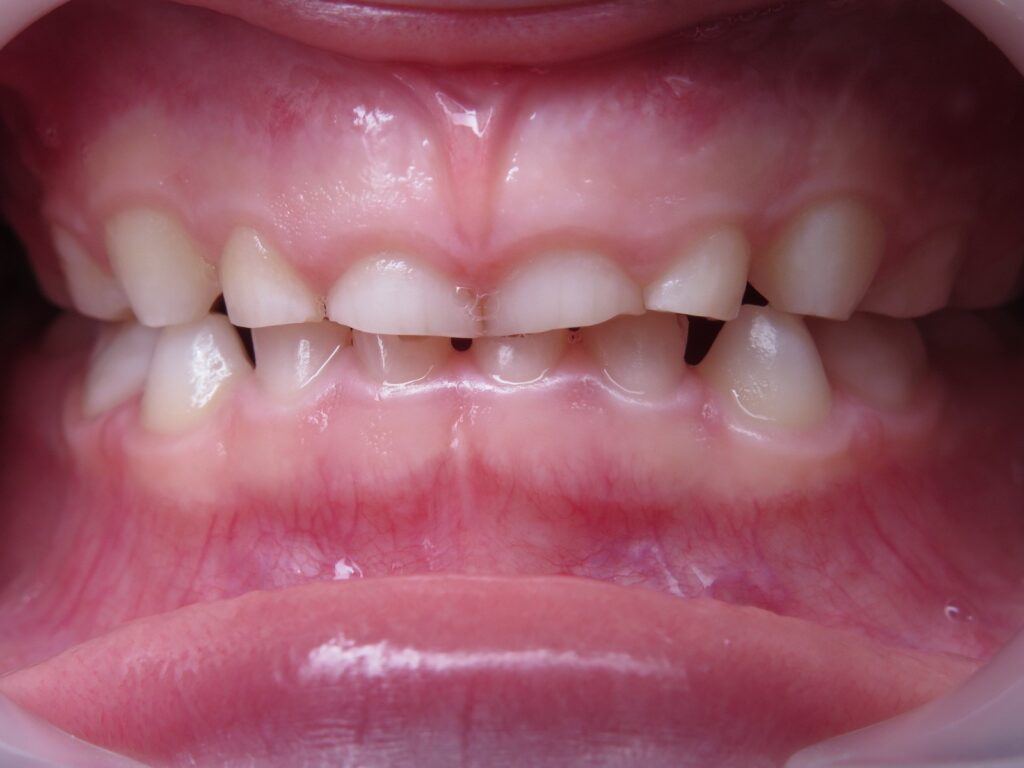

Un cas de béance :

6 mois de traitement et une élocution nettement améliorée

Traitement débuté à 3,5 ans et terminé à 4 ans